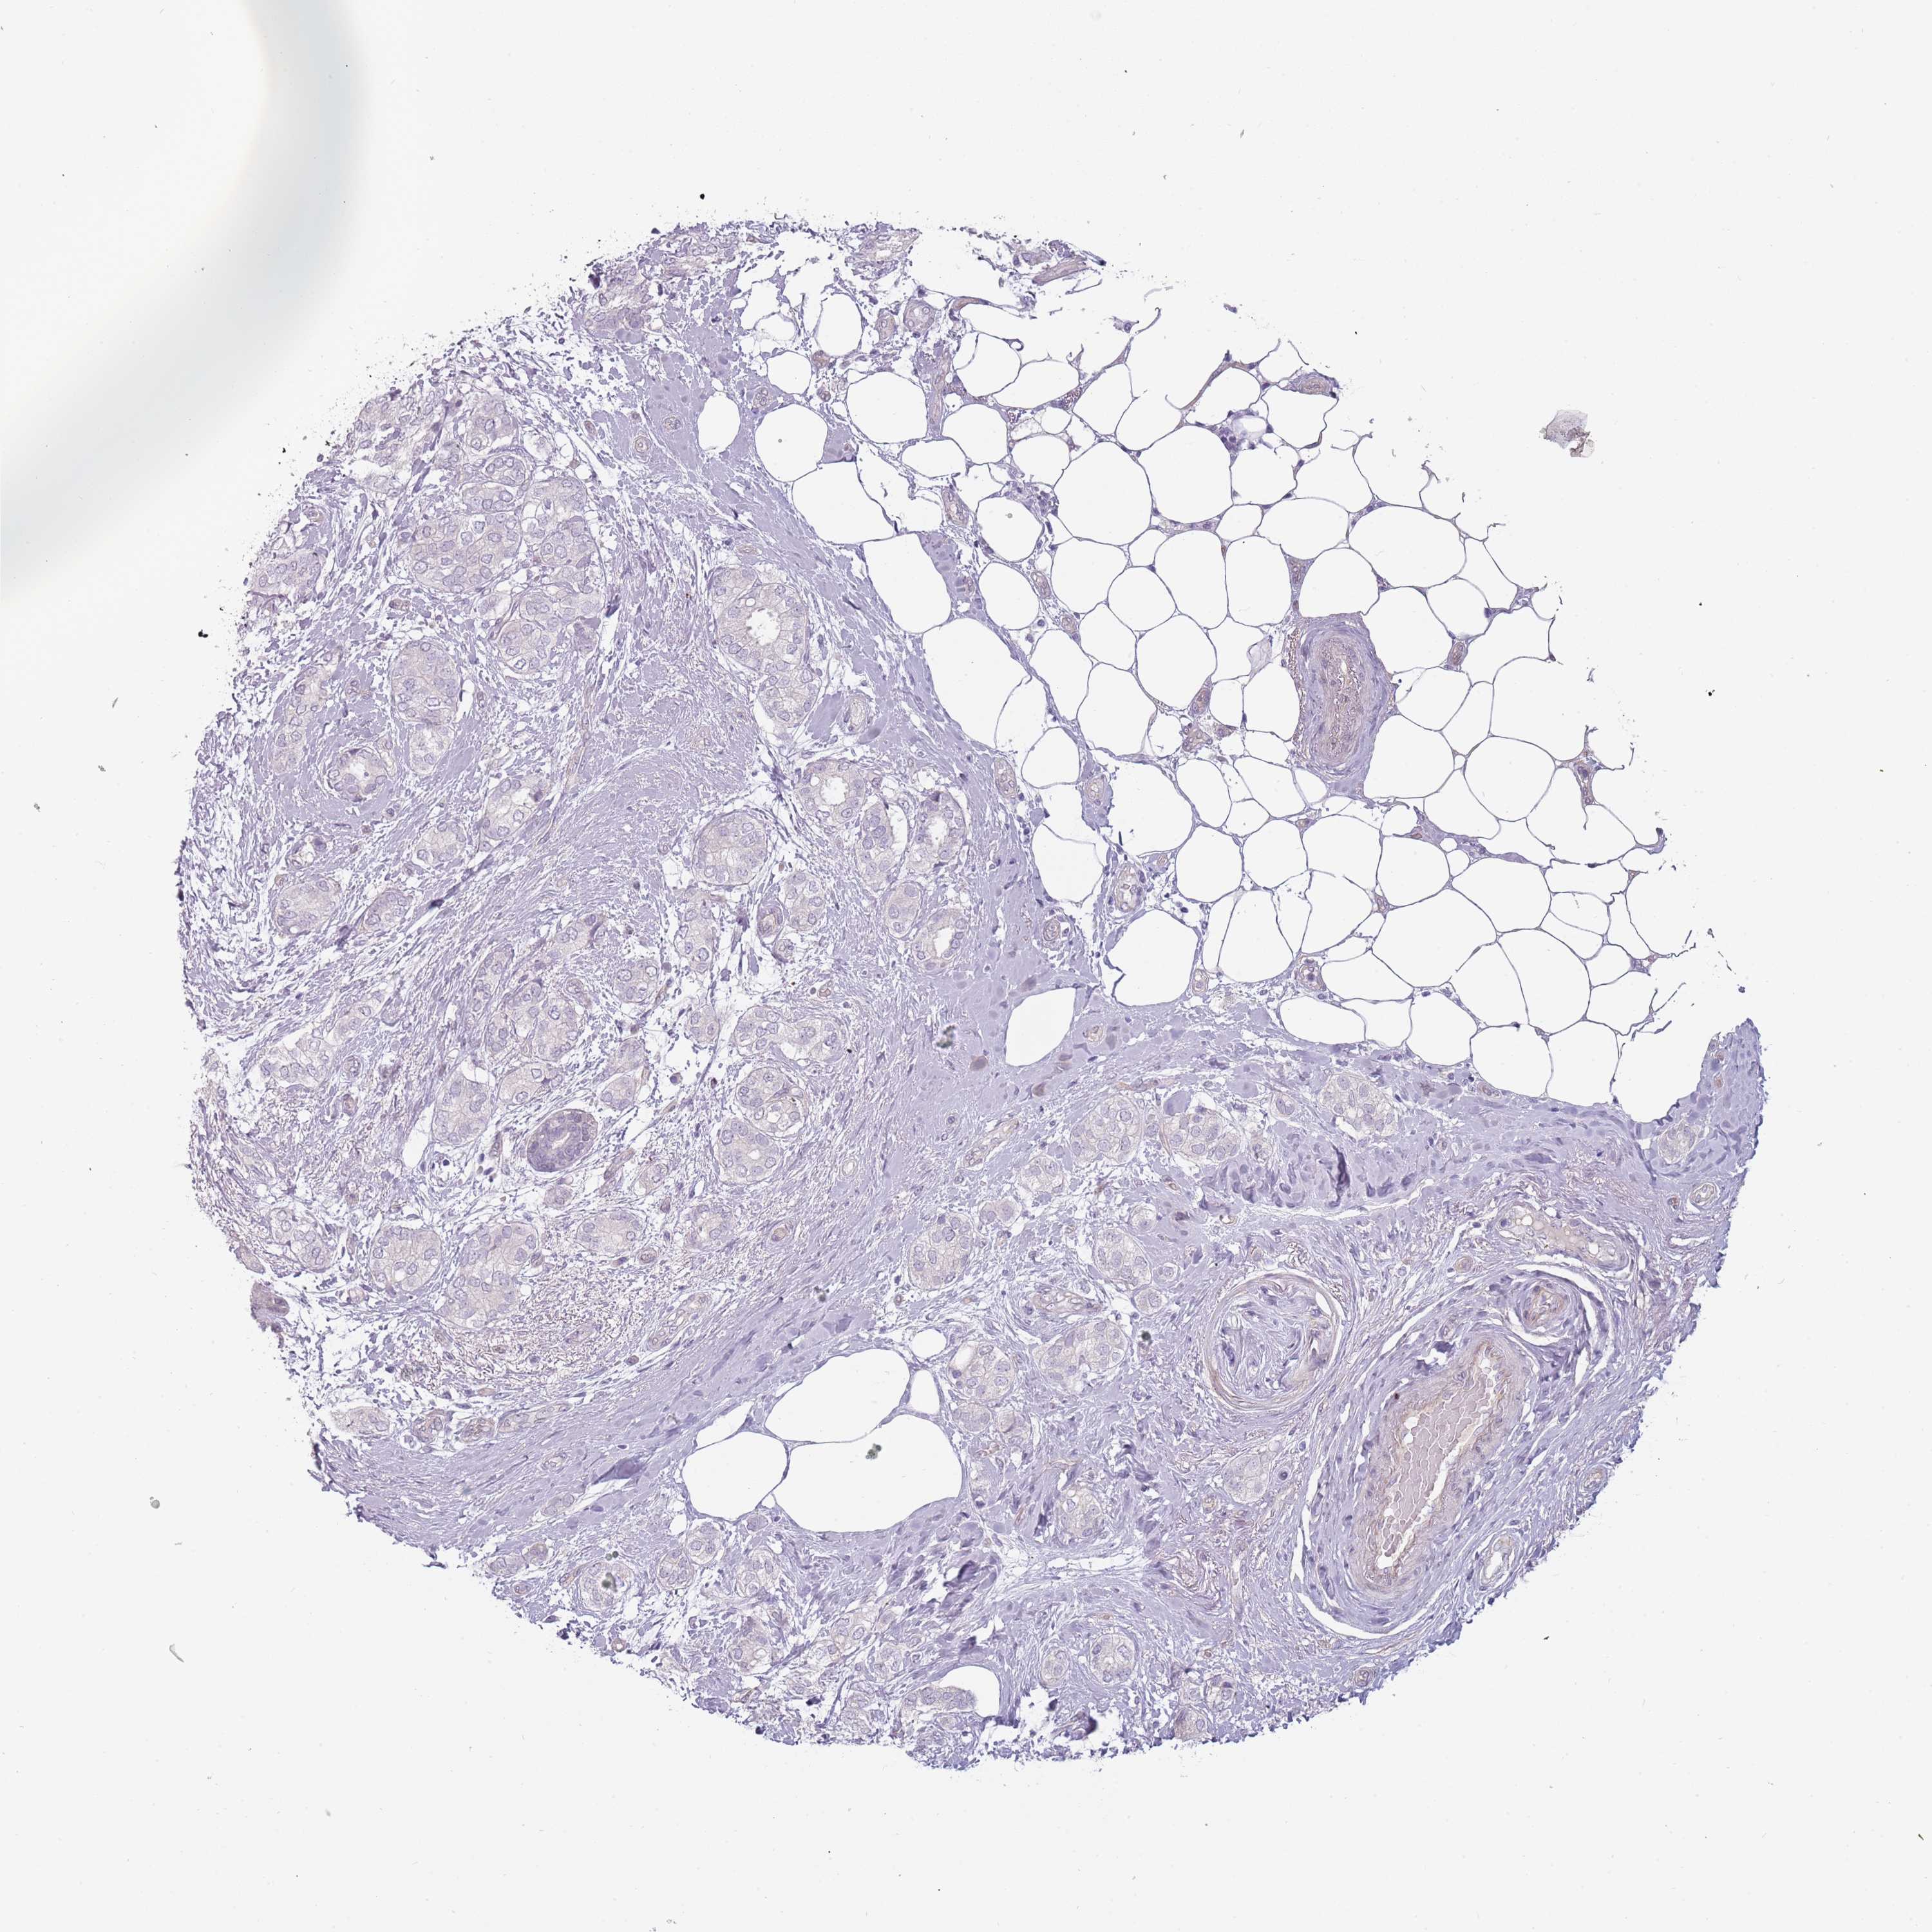

CANCER BREAST CANCER Show tissue menu

Breast cancer

Human cancer